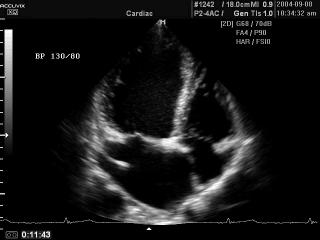

Heart (4 chamber view), B-mode

Accuvix-XQ. Heart (4 chamber view), B-mode.